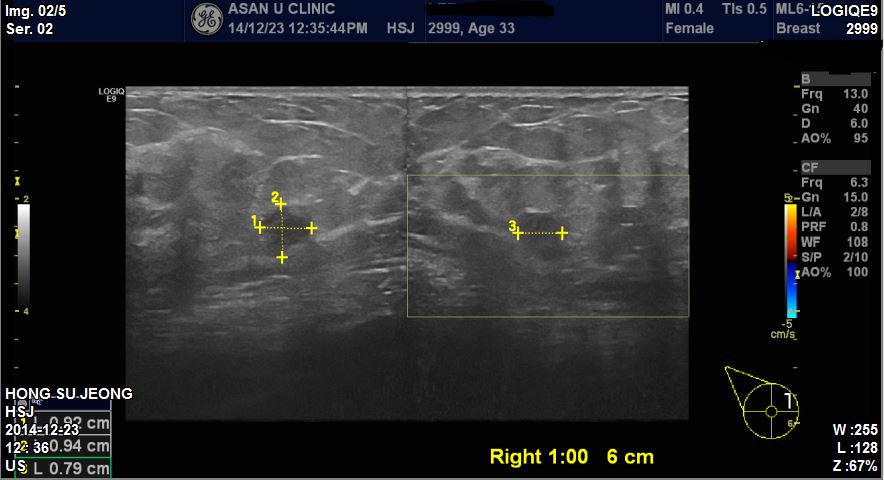

아산유외과 개원후 184번째 유방암진단.

타원 검사상 이상소견보여 내원하신 33

세 여성분이십니다

.

우측유방에 1시방향에 0.95cm

정도의 혹이있어 본원에서

조직검사 시행결과 침윤성 유방암으로 진단되셨습니다

환자분의 빠른 쾌유를 기도합니다